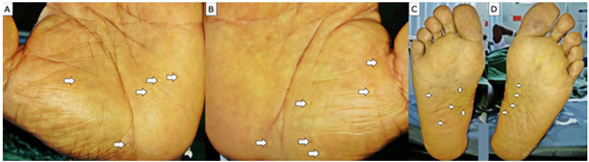

An exophytic tumor measuring 9x10cm with a verrucous surface and ulcerated margins was observed (Figure 2A and 2B) on the anterolateral side of the left thigh. Also, an ulcerated plaque of 16x14cm was observed on the anterolateral side of the upper third of the left leg (this was the largest lesion); it had irregular and hyperkeratotic margins, atrophic core and a hyperpigmented, nonpainful, brown exophytic tumor without discharge, located at the lower margin (Figure 2C). Finally, on the lateral side of the right calf, upper third, a 12x9cm hyperpigmented ulcerated plate, eroded at the center, was found (Figure 2D).

Photographs of legs A and B) anterolateral lesion of the left thigh; C) lesion on the anterolateral side of the left leg; D) lesion on the lateral side of the right calf.

Figure 2: Photographs of legs A and B) anterolateral lesion of the left thigh; C) lesion on the anterolateral side of the left leg; D) lesion on the lateral side of the right calf.

Hand and foot photograph. A and B) palmar pits; C and D) plantar pits.

Figure 3: Hand and foot photograph. A and B) palmar pits; C and D) plantar pits.

Similarly, patients with GGS may present palmoplantar pits, which are the result of partial or total absence of the stratum corneum and constitute the second most frequent skin manifestation of this condition, being found in up to 87% of cases; calcifications of the falx cerebri or the tentorium cerebelli may also occur in up to 80% of patients.17 Other less common characteristics are agenesis of the corpus callosum, mandibular prognathism, vertebral malformations, hypertelorism, congenital hydrocephalus and medulloblastomas.4,5

In the case presented here, the patient met three major criteria: multiple BCCs, palmoplantar pits, and calcifications in tentorium cerebelli and falx cerebri, which allowed establishing the diagnosis of GGS.